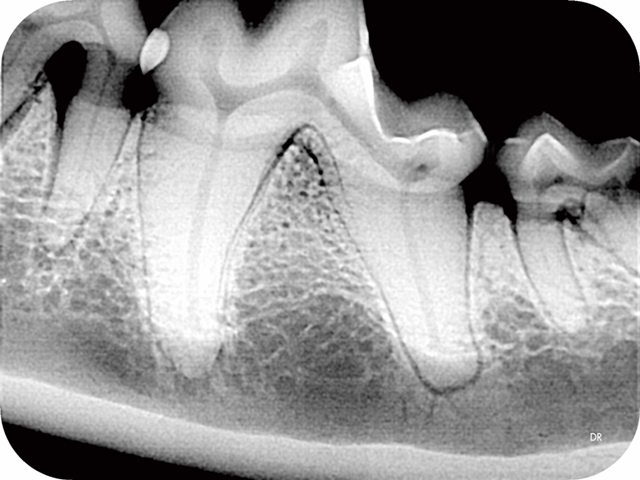

▲院内新进牙科DR设备之一

▲部分牙科DR效果展示图(可左右滑动)

什么是DR?

DR检查是影像科常用的一种检查方法,它又称为数字化X射线摄影系统,相对于传统的拍片子检查,它的辐射量更小,检查的时间更短,片子的质量也更高